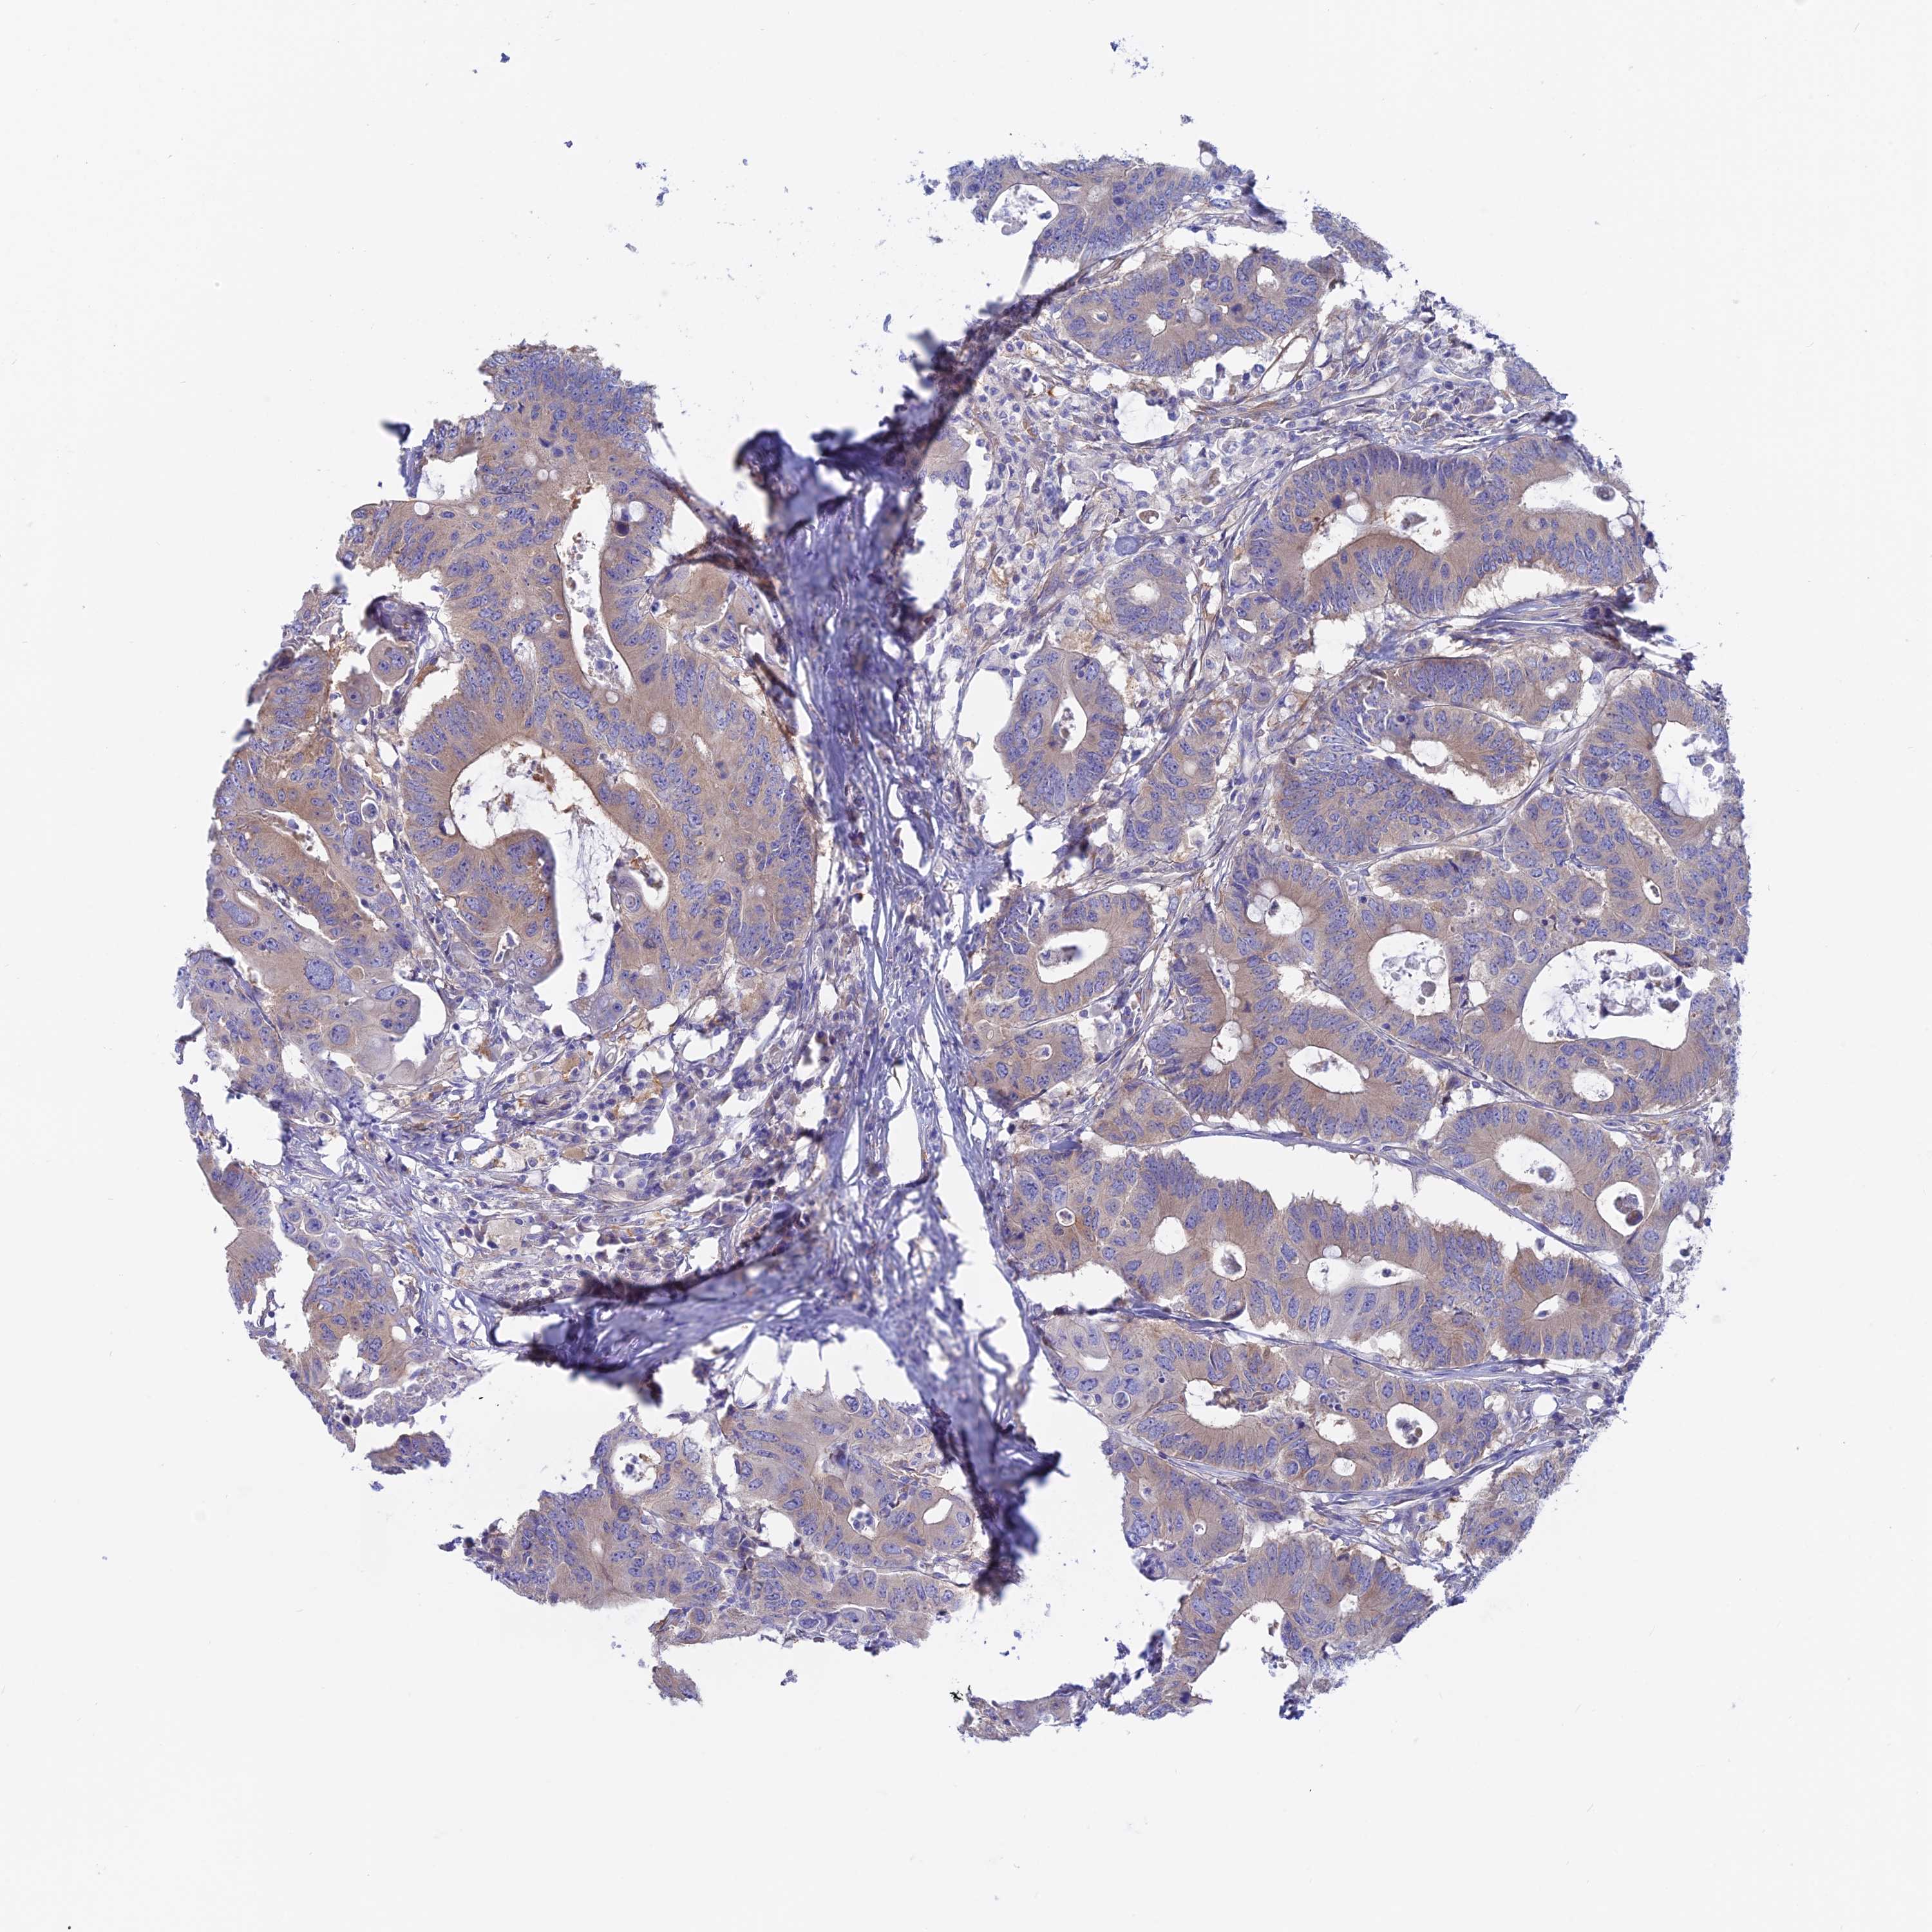

CANCER COLORECTAL CANCER Show tissue menu

Colorectal cancer

Human cancer

Colon adenocarcinoma

Rectum adenocarcinoma